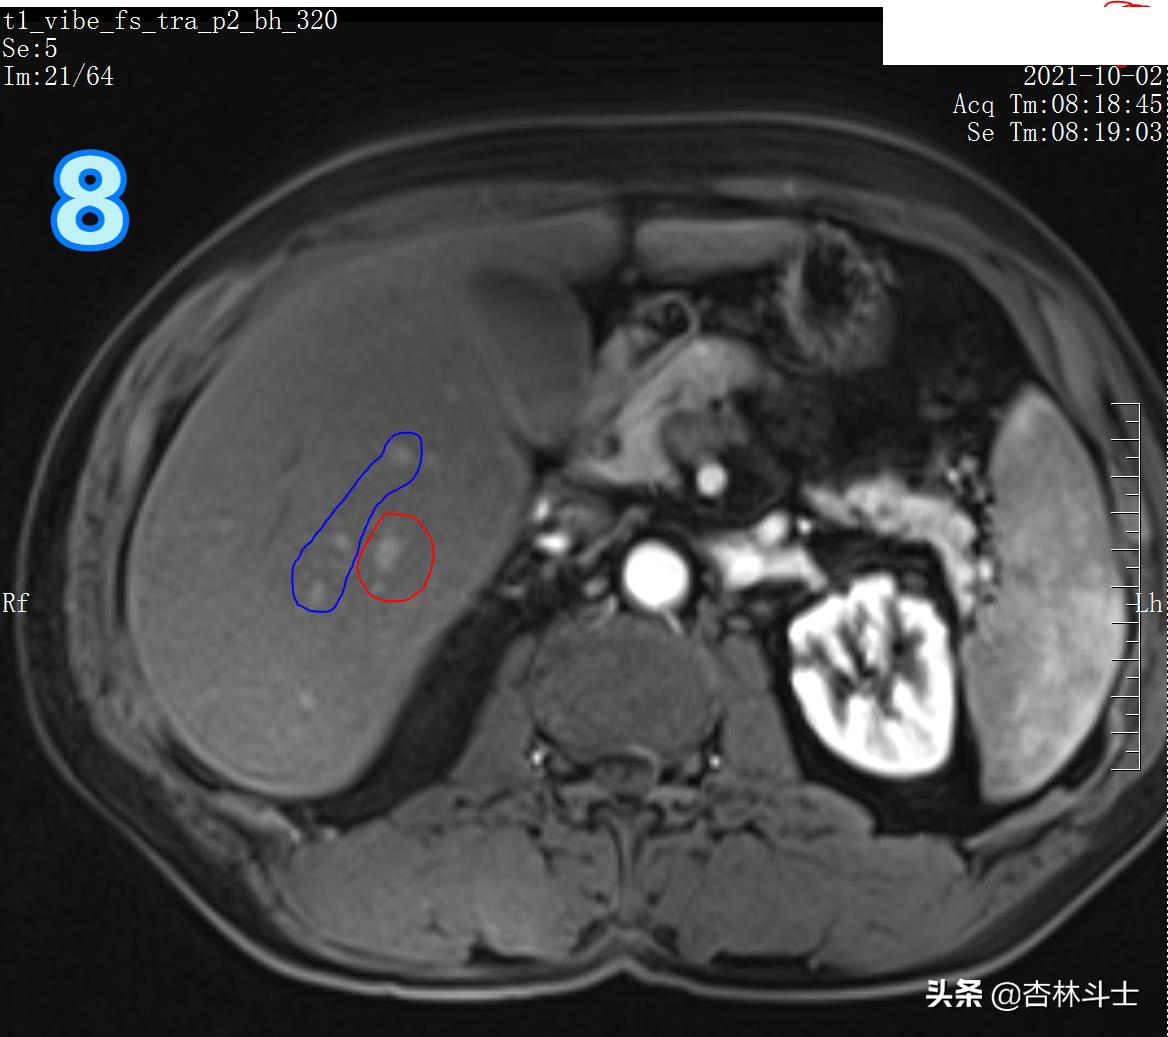

T1压脂动脉期

图8 蓝框为三根血管 ,红框为新发病灶,在T1压脂动脉期呈明显强化。